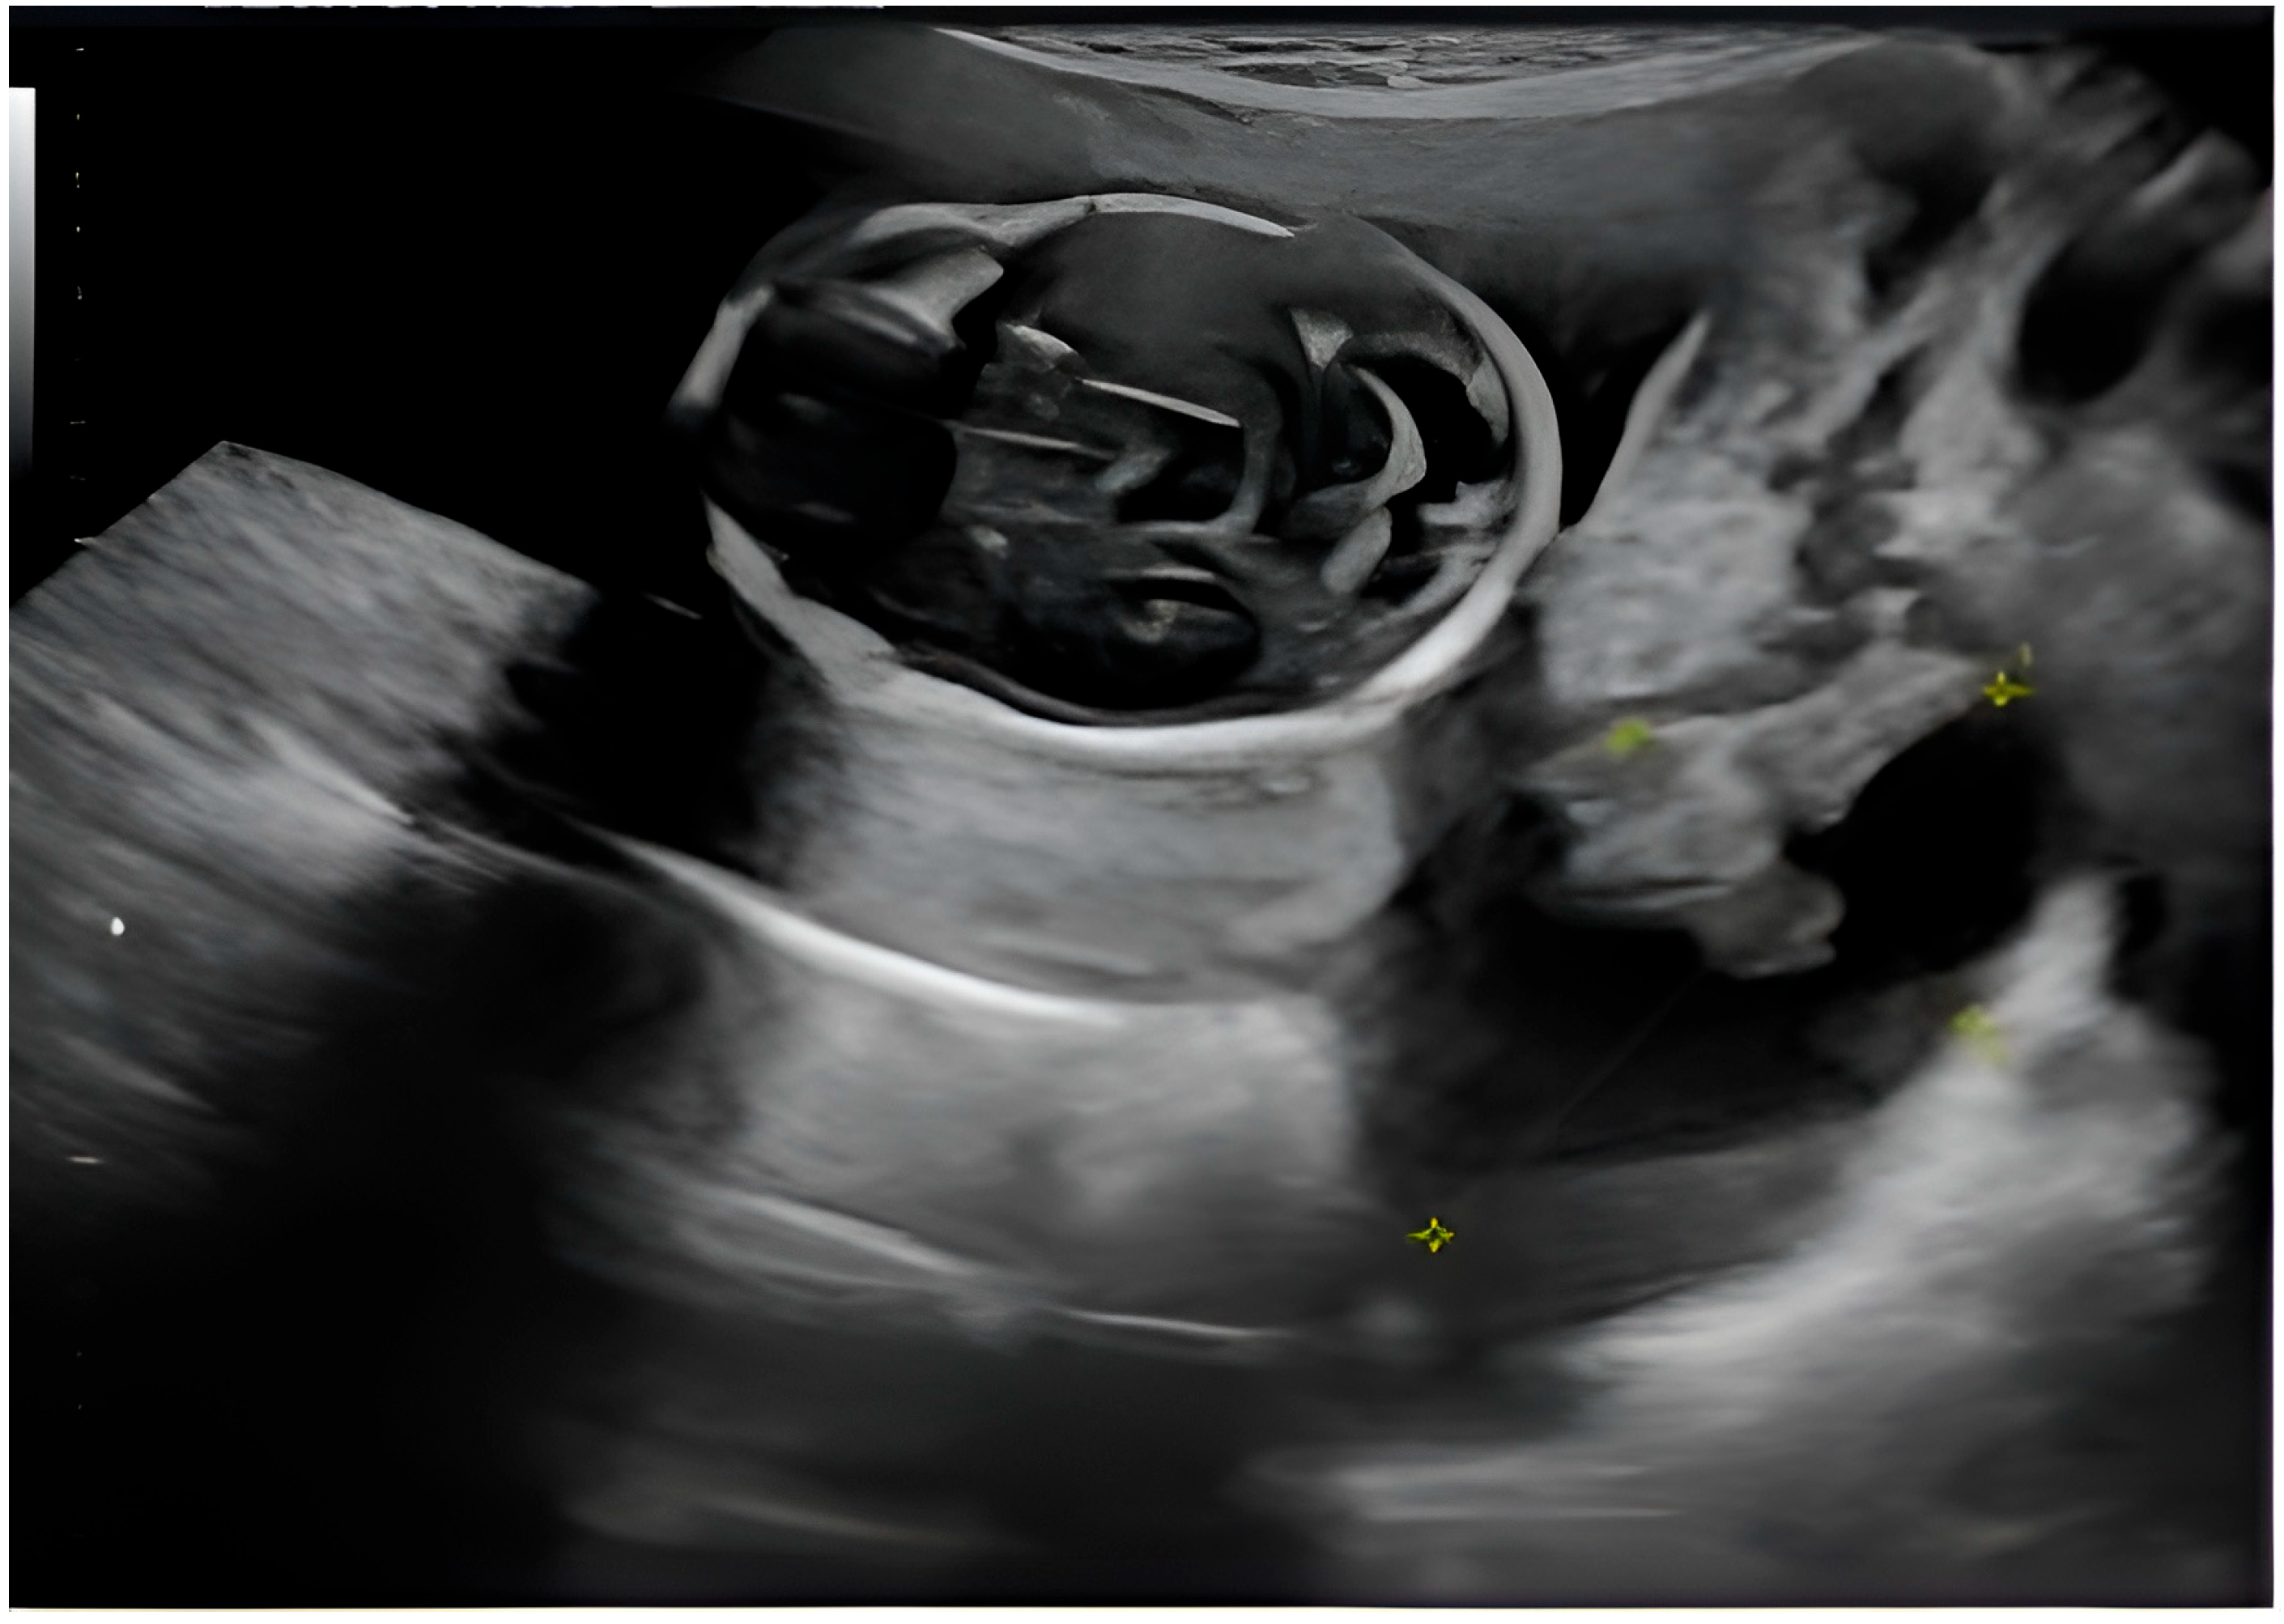

The patient had an overall good health condition. Abdominal distension was appropriate for gestational age and she reported no unusual pain, bleeding or amniotic fluid loss. The first trimester morphology showed as follows: adequate growth for gestational age, without detectable structural defects; on the right ovary—a formation suggestive of a complex ovarian cyst measuring 4.98/3.75 cm, with a mixed non-echogenic and solid component; left ovary of normal appearance (Figure 1).

It is worth mentioning that on the pregnancy confirmation ultrasound, the patient did not present any structural abnormality at the level of the adnexa and that the patient had absolutely no clinical signs or symptoms suggestive of an ovarian mass.

Approximately 3 weeks later, the patient performed a routine check-up with the attending physician, during which the following aspects were detected by ultrasound: Pregnancy 16 weeks and 2 days in progress; on the right laterouterine site an image of about 5 cm is visualized, with regular contour, mixed content, multiple intracystic vegetations, of which the largest was 3.4/3.2 cm, with Doppler signal present and several small vegetations of approximately 0.2 cm; on the left laterouterine site—an image of 3/1.8 cm, with regular contour, intracystic vegetation and Doppler signal; no free intraperitoneal fluid was detected. Following this ultrasound, the suspicion of ovarian neoplasm was raised and the patient was advised to undergo more advanced imaging investigations (Figure 2).

A single, well-defined, predominantly anechoic cystic structure is seen in the right adnexal region. The lesion is thin-walled, with no evidence of papillary projections or solid mural nodules. Possible fine internal septation or debris layering may be present (as seen in the coronal and transverse 2D views), suggesting a complex cyst, although the overall appearance remains largely cystic. The 3D reconstruction provides a spatial view of the lesion, showing a rounded, fluid-filled structure. No calcifications or highly irregular wall thickening are visible (Figure 1).

The central structure appears anechoic to hypoechoic, indicating that it is filled with fluid. The internal appearance of the cyst seems to have some irregularity or septation, which may suggest a complex cyst. The red and blue signals in the walls or septa show vascularization. This Doppler scan helps to assess blood flow. In this image, peripheral flow is visible (Figure 2).

Figure 1. Transvaginal pelvic ultrasound—2D mode (top left, top right, bottom left) shows the right adnexal mass and its mixed components (the yellow arrows indicate internal vegetations, while the blue one points to intra-cystic fine septation) and 3D volume rendering (bottom right) allowing assessment of the lesion in a spatial manner.